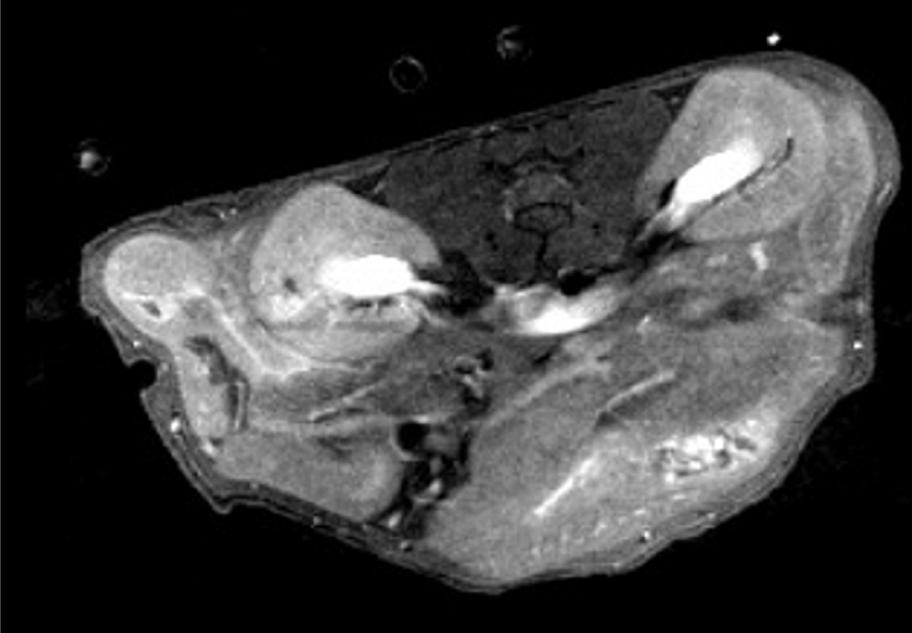

Whale and dolphin post-mortem imaging could breathe new life into marine conservation.

Researchers at City University of Hong Kong have developed a new, non-invasive imaging approach to examine the remains of beached marine mammals, like whales and dolphins. The approach, called virtopsy, was described in the journal Frontiers in Marine Science and can be used to determine the cause of death. It can also gather useful information about the animal before it died, such as its general health, as well as if it suffered human impacts, such as vessel collision or marine pollution.

Virtopsy uses modern imaging techniques to examine dead marine mammal remains. It is performed before conventional necropsy, the animal equivalent of human body-opening autopsies, or can even replace it in some cases.

Kot and his team have performed virtopsies on more than 200 beached marine mammals using post-mortem computed tomography (PMCT) and post-mortem magnetic resonance imaging (PMMRI). The work shows that PMCT identifies bone lesions, foreign bodies, pathological gas formation and organ trauma better than conventional necropsy. PMMRI is

better at identifying soft tissue injury, organ trauma and non-traumatic pathology.

The team also found that PMMRI provides more information on decomposed brains than PMCT. Additionally, it should be used in conjunction with PMCT to detect soft tissue lesions and brain pathologies, as PMMRI alone is more prone to showing unwanted artefacts from gas and foreign bodies.

The team uses modern imaging techniques to examine dead marine mammal remains.